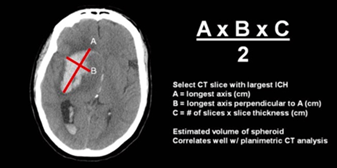

ICH volume measurement

- 1/2 x A x B x C